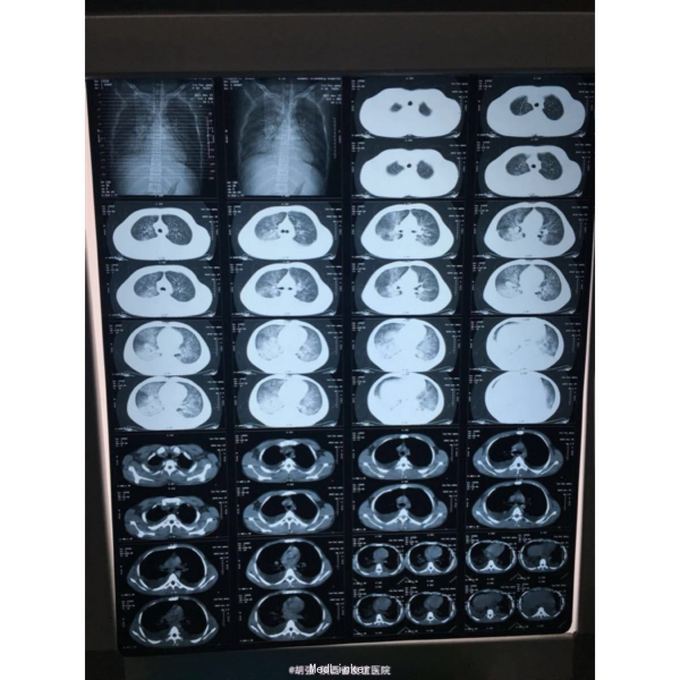

查体:口唇无发绀,咽充血,双侧扁桃体2度大,表面可见脓胎。两肺呼吸音粗糙,可闻及管状呼吸音。余查体无明显异常。 辅助检查:血常规提示白细胞及血小板明显低于正常值,肝功提示转氨酶升高。凝血系列:PT、APTT时间明显延长。T sport试验弱阳性。10月份胸部CT平扫未见明显异常。10月26日及12月12日胸片未见明显异常。12月19日胸部CT提示:两肺斑片状阴影,两侧胸腔积液。